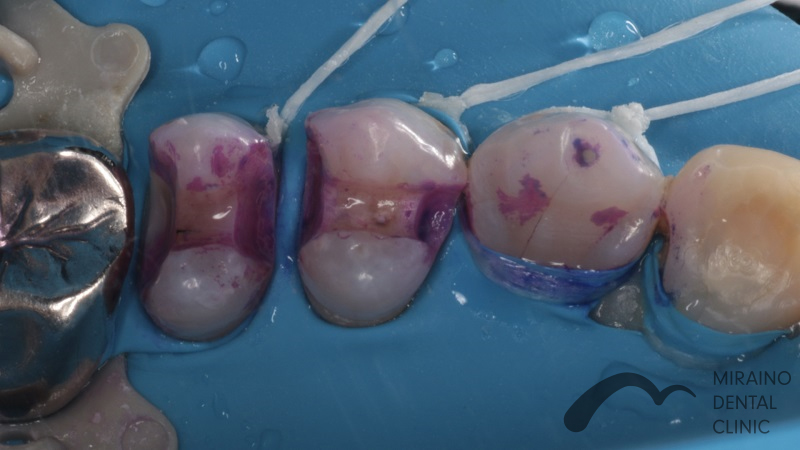

詰め物・メタルフリーインレーの症例

Case1

| 施術名 | 詰め物・メタルフリーインレー |

| 施術の概要 | 定期検診の際に、レントゲンを撮影した際に 5年前以上に治療した銀歯に隙間があることを衛生士が見つけました。 沁みる、噛むと痛いといった症状はありませんでしたが 次回再発した際は神経を取らないといけなくなる可能性が高いため 、 なるべく再発しにくい歯科治療を希望され、メタルフリーインレーによる修復治療を行いました。 |

クリックして詳細を表示

| 施術の内容 | 銀歯は歯より硬すぎる、歯を腐食させる作用があることから約5年で再発すると言われています。 ラバーダムを用いて唾液による接着不良のリスクを排除し完全に水分を排除した状態でムシ歯治療を行います。 型取りを行い、技工士によって汚れの付きにくいセラミックで形を再現している。 |

| 1歯あたりの治療費 | 1歯:50,000円 |